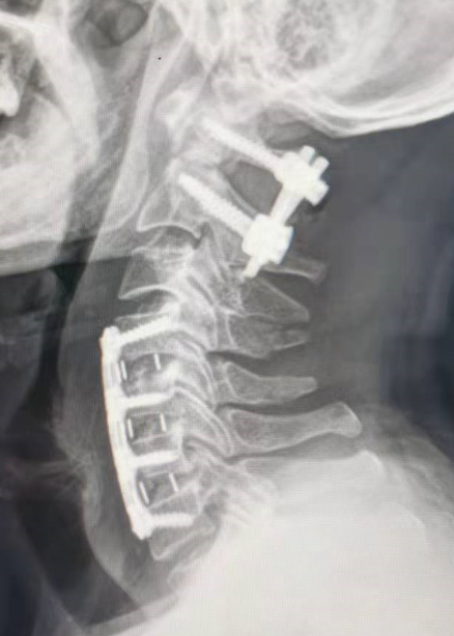

朱希田副主任医师组织科室医护团队进行了详细的讨论分析,决定先予俯卧位行“后入路寰枢椎骨折切开复位+椎弓根钉内固定术”,再仰卧位行“前入路颈4-5、颈5-6、颈6-7椎间盘切除+颈椎管减压+颈椎椎间植骨融合+颈4-颈7椎体钛板螺钉内固定手术”。

凭借娴熟的手术技术,医生成功地在复杂的寰枢椎上置入椎弓根螺钉,并将脱位的齿状突骨折和寰椎完全复位,成功实现了精准置钉和完全复位,且手术创伤小,出血少,在小切口下顺利完成;前路多节段颈椎手术也很顺利,前路+后路手术出血仅100-200ml。术后患者很快恢复清醒,四肢开始活动,术后8小时开始进流质饮食,术后第3天便可下地行走,之后各项生活逐渐恢复自理。